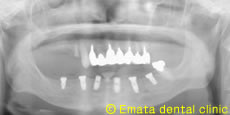

歯は1本しかないが取り外しの義歯はいやだ72歳女性

昔のように自分の歯で噛みたいとう希望でした。入れ歯が合わなくて、食事や生活に困っていらっしゃる方には、インプラントは朗報です。